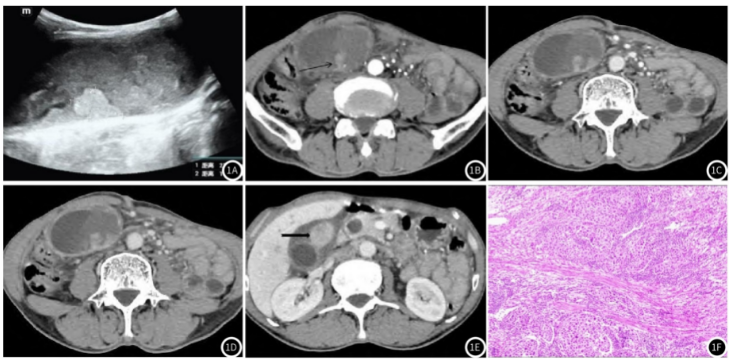

腹部超声示:胆囊增大,壁欠光滑,壁见多个稍强回声,呈“菜花状”,与胆囊壁呈宽基底相连,较大者约2.4cm×1.4cm,其周围弱回声包绕,CDFI:稍强回声及弱回声内未见确切血流信号,考虑实性占位,胆囊Ca待排(图1A)。

腹部CT

扫描示:胆囊形态不规整,体积明显增大,腔内密度不均匀增高,壁不规则增厚,以胆囊体及胆囊底为主,并可见结节影向腔内突出,较大者最大径约1.8cm,增强扫描动脉期呈不均匀强化,CT值约65HU,胆囊腔内及周围见迂曲增粗血管影,门静脉期CT值约75HU,延迟期呈均匀强化,CT值约79HU;胆囊周围见多个肿大淋巴结,较大者约3.2×2.4cm,并不均匀强化;邻近肝内见环形异常强化结节影,最大径约1.5cm;病灶与十二指肠、结肠肝曲分界不清;考虑为胆囊癌

伴淋巴结、肝脏转移(图1B-1E)。

图1 A-图1F胆囊肝样腺癌;图1 A超声图像示胆囊腔内“菜花状”稍强回声;图1B CT增强扫描动脉期示胆囊壁不均匀增厚并呈结节状向腔内突出(箭头所示),呈不均匀强化;图1C CT增强扫描静脉期示病灶持续强化;图1D CT增强扫描延迟期示增厚胆囊壁及结节呈均匀强化;图1E CT增强扫描示胆囊前份肿大淋巴结(羽箭所示);图1F病理图片示肿瘤内见肝样分化区和腺癌分化区